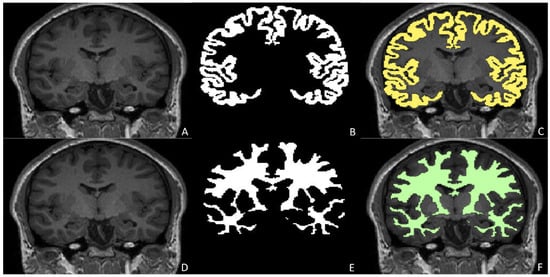

Anatomical Segmentation and Quantitative Assessment in Pediatric Neuroradiology

- Grimm, F.; Edl, F.; Kerscher, S.R.; Nieselt, K.; Gugel, I.; Schuhmann, M.U. Semantic Segmentation of Cerebrospinal Fluid and Brain Volume with a Convolutional Neural Network in Pediatric Hydrocephalus-Transfer Learning from Existing Algorithms. Acta Neurochir. 2020, 162, 2463–2474. [Google Scholar] [CrossRef]

- Billot, B.; Greve, D.N.; Puonti, O.; Thielscher, A.; Van Leemput, K.; Fischl, B.; Dalca, A.V.; Iglesias, J.E. SynthSeg: Segmentation of Brain MRI Scans of Any Contrast and Resolution without Retraining. arXiv 2021, arXiv:2107.09559. [Google Scholar] [CrossRef]